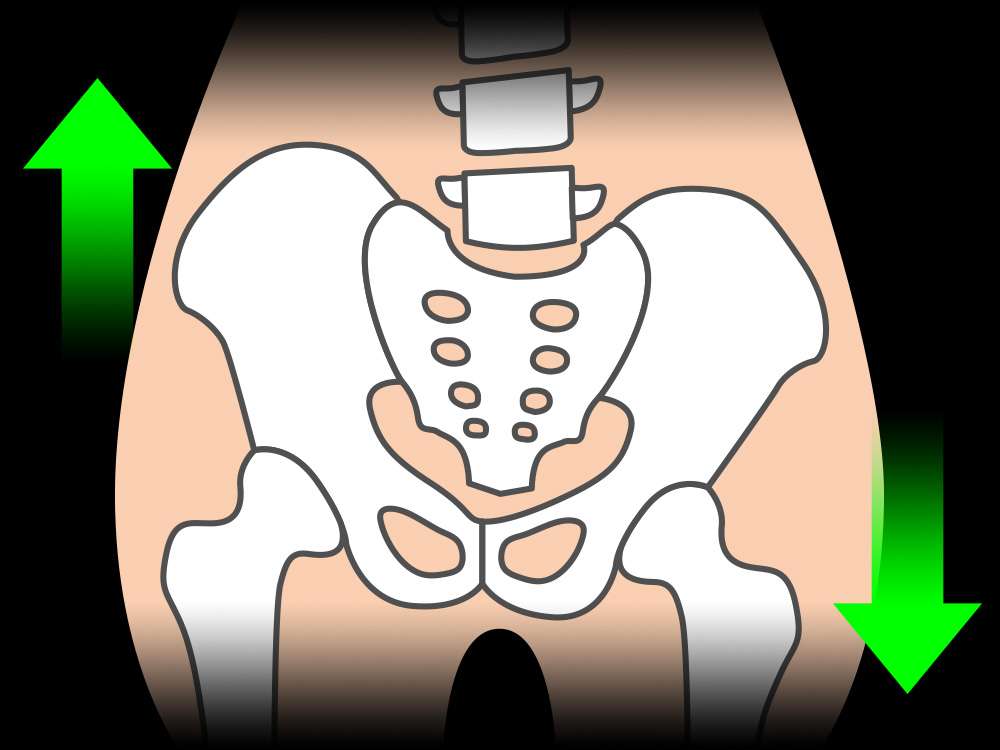

骨盤の歪みに気をつけよう!

骨盤の歪みに気をつけよう!

さて、今日は骨盤の歪みの原因についてお伝えしようと思います😊

身体全体を支える骨格、土台となる骨格である骨盤。

骨格や骨盤が歪むと、身体のバランスも崩れてきてしまいます。

【歪む原因】

体の重い部分を支えるために骨盤が前後どちらかに引っ張られて傾いたり、これまで染み付いた普段の姿勢や動作の癖により、どちらか片方だけに負荷がかかったり、どちらかの筋肉がうまく使えていない影響から、筋肉の柔軟性や筋力には左右差が生まれ、歪んでしまいます。

では、骨盤が歪むと、身体にさまざまな影響を及ぼす恐れがあります。